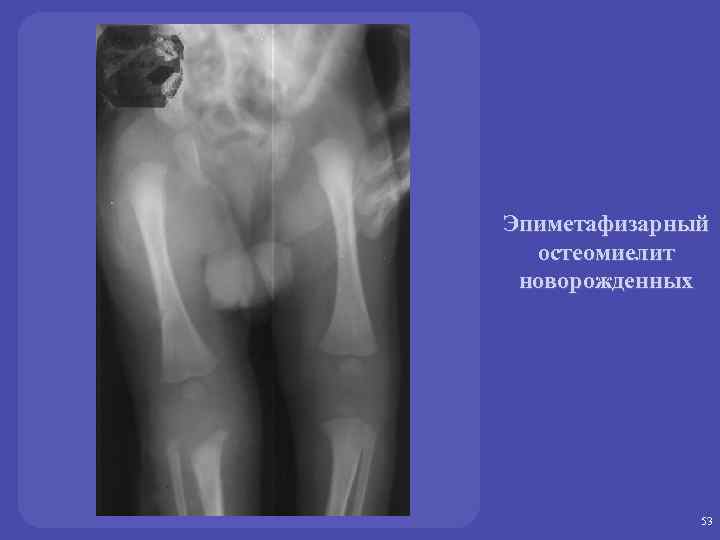

Эпиметафизарный остеомиелит новорожденных 52

Эпиметафизарный остеомиелит новорожденных 53